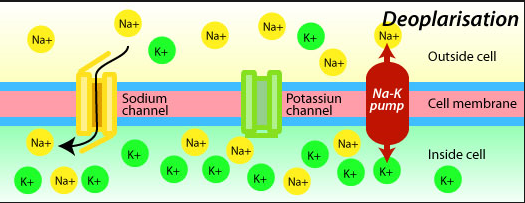

inside N = Nitrogen H = Hydrogen